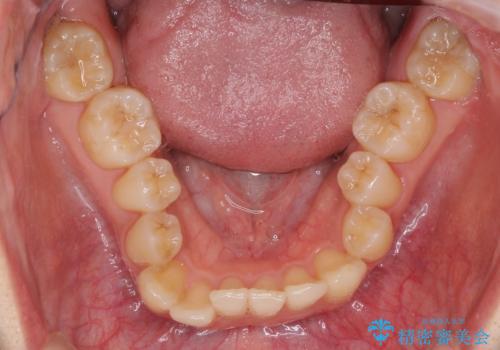

反対咬合は上顎骨の幅が下顎骨よりも小さいことが原因なので、拡大装置により骨幅を広げて上下関係を改善し、その後インビザラインにて歯並びを整えることとしました。

反対咬合が改善され、食いしばり癖もなくなり、顎関節の負担が軽減されました。

上顎骨を拡大したことで前歯に隙間ができ、1ヶ月ほど恥ずかしい時期がありましたが、しっかりとした咬み合わせに仕上がり、患者様には大変満足していただきました。